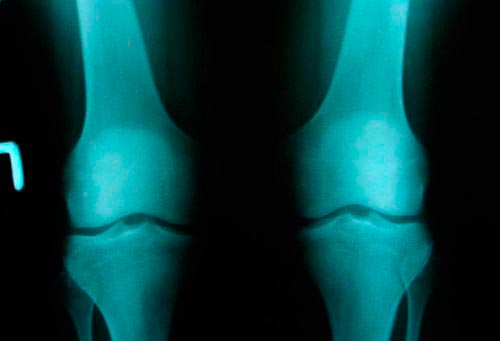

1 степень проявляется в виде незначительного нарушения подвижности сустава. Рентген показывает небольшое разрастание кости по краям впадины самого сустава, его щель сужена, имеются районы оссификации хрящевой ткани.

При артрозе коленного сустава 2 степени возникает грубый хруст при движении. Наблюдается общая невозможность передвигаться. При проведении рентгена видны большие области костных разрастаний, начинается субхондральный склероз, щель сустава сужается в два-три раза, по сравнению с показателями нормы.

Гонартроз коленного сустава 3 степени характеризуется утратой полноценного движения. Остаются только покачивания пораженным суставом. Он очень сильно деформируется. После рентгена можно увидеть отсутствие суставной щели. Сама поверхность расширена из-за разрастания ее краев. Деформирование остро выраженное, имеется уплотнение обоих эпифизов.

Рентгенография проводится в двух проекциях, чтобы получить изображение со всех сторон. Для достоверного отображения патологических процессов часто проводится многосторонний рентген здорового колена. После этого производится сравнение.